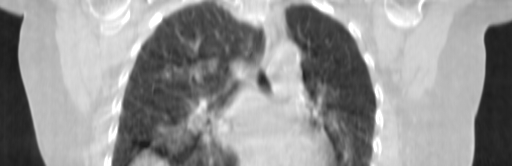

ClearRT® Images